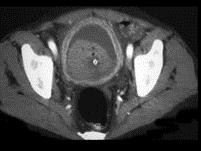

女,36岁,血尿1周余,请根据所示图像,选择最可能诊断 ( )A、膀胱癌B、输尿管癌C、膀胱结石D、膀胱息肉E、膀胱血块

问题 女,36岁,血尿1周余,请根据所示图像,选择最可能诊断 ( )

选项 A、膀胱癌 B、输尿管癌 C、膀胱结石 D、膀胱息肉 E、膀胱血块

答案 E